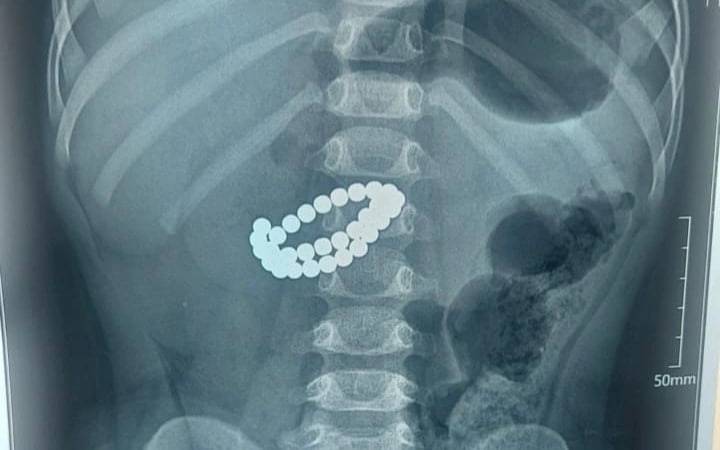

Qozog‘istonda bolaning ichagidan 31 ta magnit chiqarib olindi

Farg‘onalik 2 yoshli qizaloqning qornidan 135 ta magnit sharcha chiqarib olindi